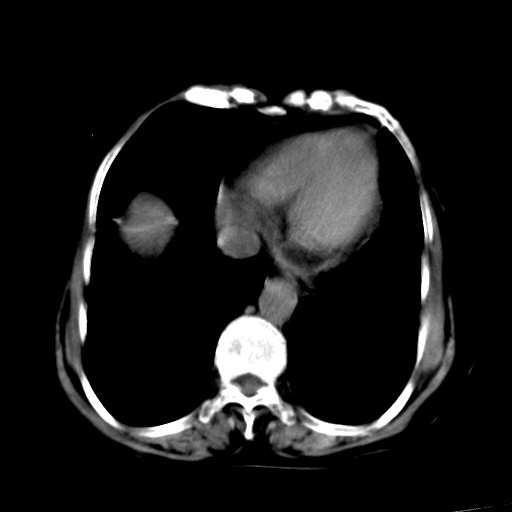

以下是引用杀毒软件在2009-3-4 17:38:00的发言:[br]为何没有喝照影剂呀? 胆总管及肝内胆管扩张,增强吧。[br][br]考虑-----十二指肠占位----建议----十二指肠镜检查[br][br]

以下是引用jiangjing在2009-3-4 17:45:00的发言:[br]低位胆道梗阻。十二指肠降段局部管壁增厚。扫描效果不理想,建议ct增强及ercp。

以下是引用杀毒软件在2009-3-4 17:38:00的发言:[br]为何没有喝照影剂呀? 胆总管及肝内胆管扩张,。增强吧。[br][br]考虑-----十二指肠占位----建议----十二指肠镜检查[br][br][br][br][本贴已被 杀毒软件 于 2009-3-4 17:56:38 修改过]